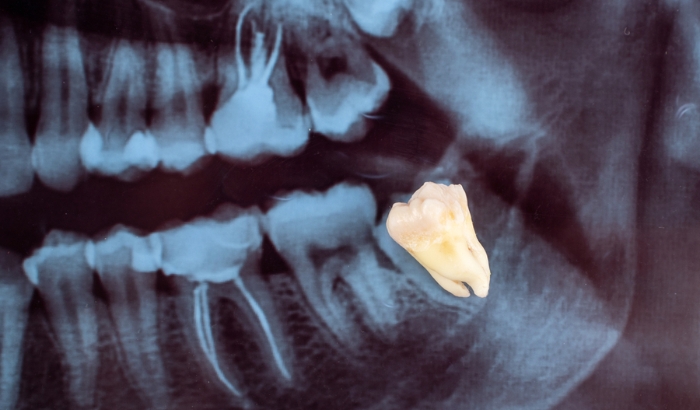

Why experts now say not to remove your wisdom teeth

Learn why experts now advise against removing wisdom teeth and the potential risks involved with the procedure. Wisdom teeth coming through? Here’s what you need to know Wisdom teeth, or…